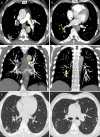

Results: The study population comprised 82 men and 19 women, with a mean age of 64.1 years ± 15.0 (95% confidence interval [CI]: 60.4, 67.6) years. CT pulmonary angiography was performed 19.8 days ± 6.1 (95% CI: 18.1, 20.2) after symptom onset and 10.5 days ± 3.8 (95% CI: 10.2, 12.9) after admission. Of 101 patients, 41 had PTE (40.6%). PTE was mostly bilateral or only right (37/41 [90.2%]), mainly involved segmental (37/41 [90.2%]) or subsegmental (25/41 [61.0%]) arteries and affected mainly the branches of the lower lobe (30/41 [73.2%]). Parenchymal segments supplied by segmental arteries with PTE showed a prevalent consolidation pattern (25/37 [67.6%]). Deep vein thrombosis was present only in five of 41 (12.2%) patients. Comparing groups with and without PTE, no significant difference was observed in age, sex, symptom onset, comorbidities, tumor history, use of respiratory supports, activated partial thromboplastin time, prothrombin time, and deep vein thrombosis. Conversely, differences were evaluated in CT lesion score (15.7 ± 1.4 [95% CI: 15.3, 16.1] vs 14.1 ± 1.1 [95% CI: 13.8, 14.4]; P = .035), d-dimer level (P < .001), lactate dehydrogenase level (P < .001), and C-reactive protein level (P = .042).

Conclusion: PTE in COVID-19 involves mainly the segmental and subsegmental arteries of segments affected by consolidations in patients with more severe lung disease. The authors hypothesize that the development of PTE in COVID-19 might be a pulmonary artery thrombosis because of severe lung inflammation and hypercoagulability rather than thromboembolism.© RSNA, 2020.